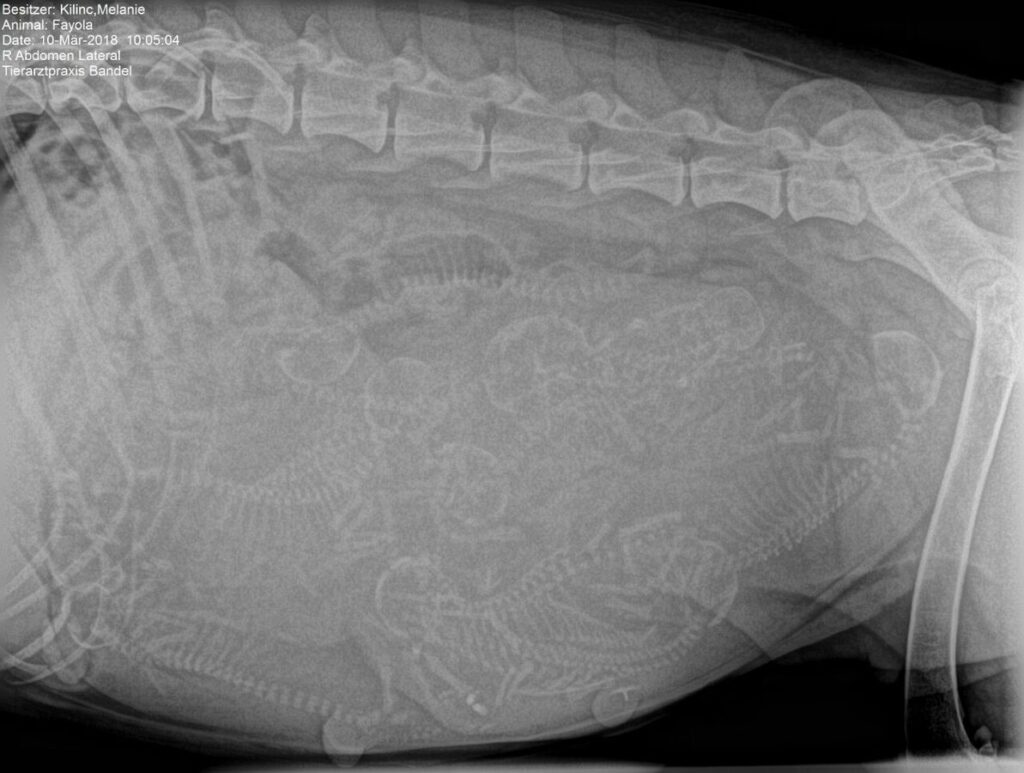

Fayola sieht aus wie ein Luftballon 😀 Jetzt sind es nur noch ein paar Tage bis zu unserem A- Wurf. Obwohl sie vor ein paar Tagen doch eher ruhig war, ist sie jetzt wieder total aufgedreht und rennt und spielt gerne wie früher, nur alles sehr langsam. Kein Wunder bei fast 8 kg Gewichtszunahme in den letzten Wochen. Am Samstag waren wir zur Herpesimpfung und zum Röntgen. Fayola war mega entspannt bei unserem Tierarzt. Auf dem Röntgenbild haben wir zehn Welpen gezählt und einer hat sich evt. versteckt, da waren wir uns alle nicht sicher, aber unsere Dicke wird ihr Geheimnis ja bald lüften Wir sind alle sehr aufgeregt und freuen uns riesig auf die Kleinen .